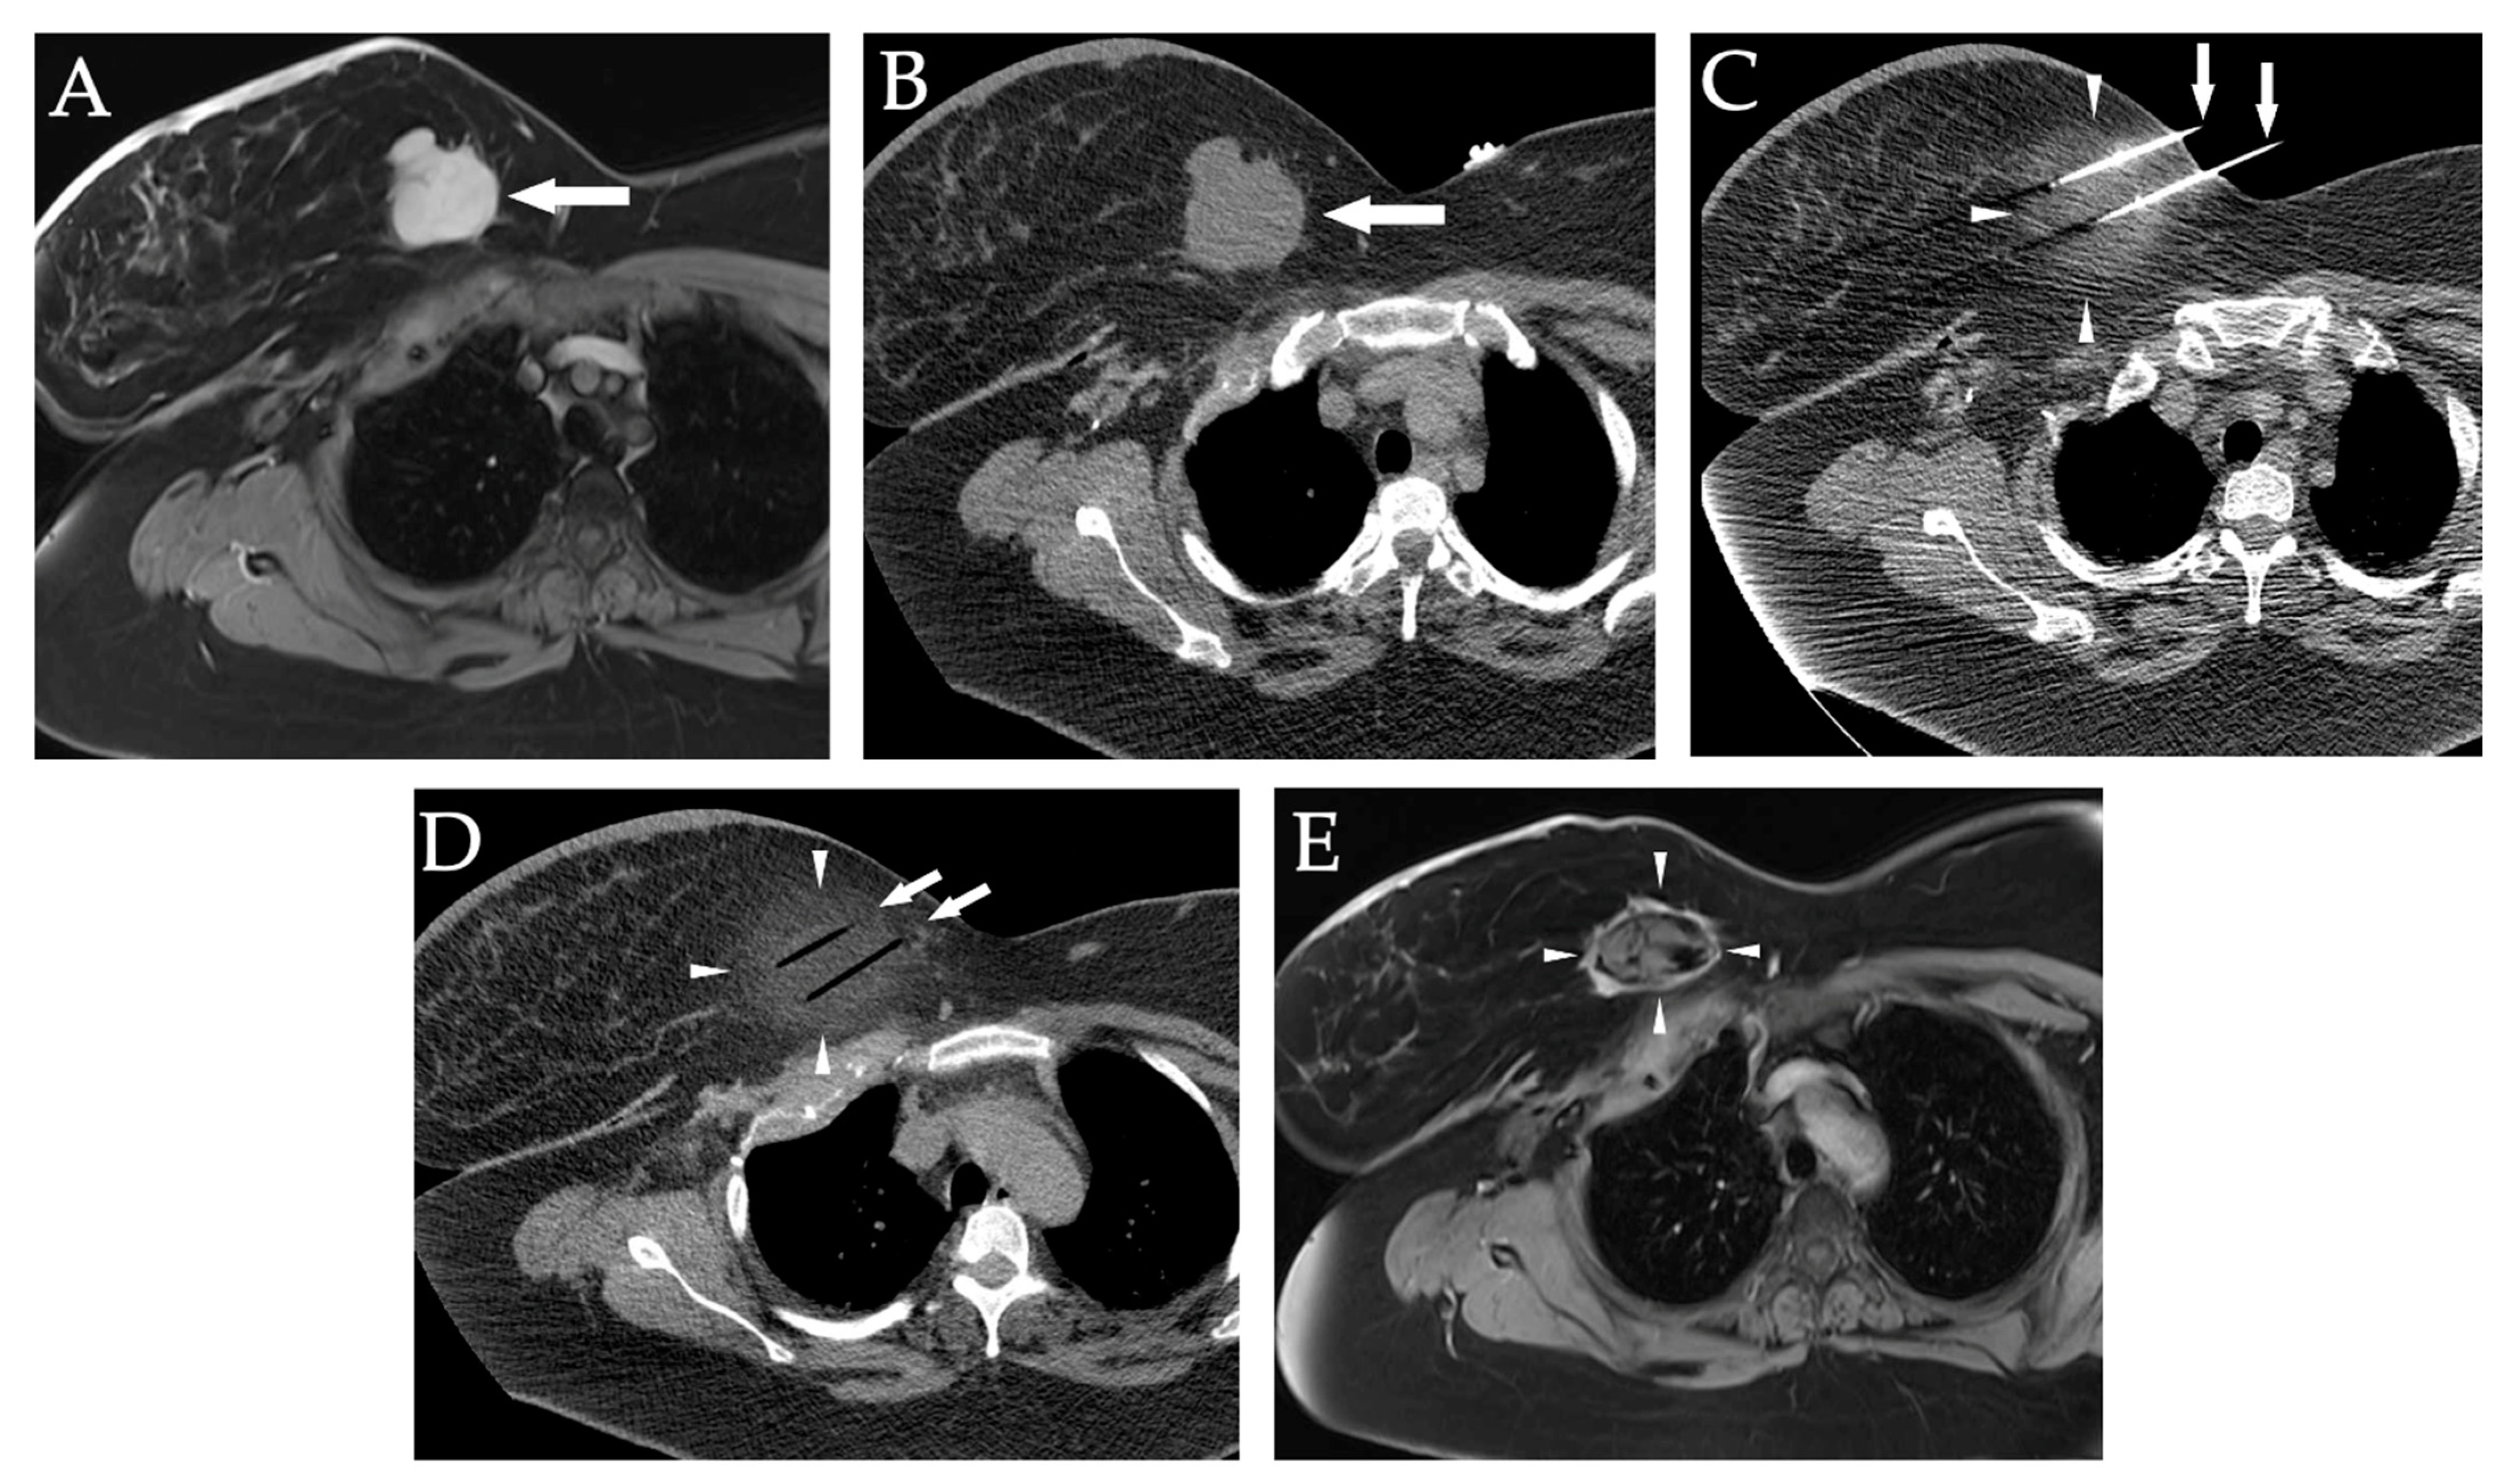

12. Primary and Metastatic Soft Tissue Tumors